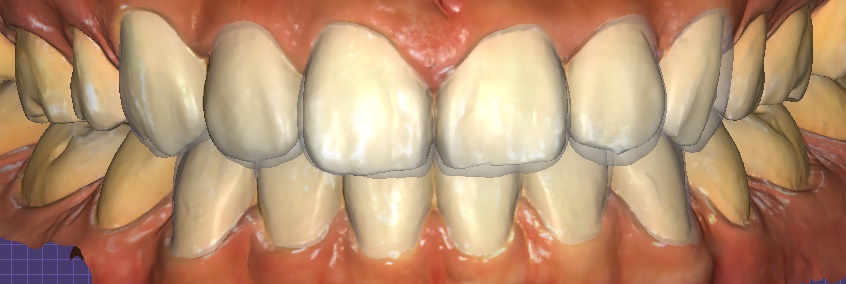

① Digital scan & design

– Precise data acquisition with an intraoral scanner → 3D design and simulation

Object Zero laminate simulation